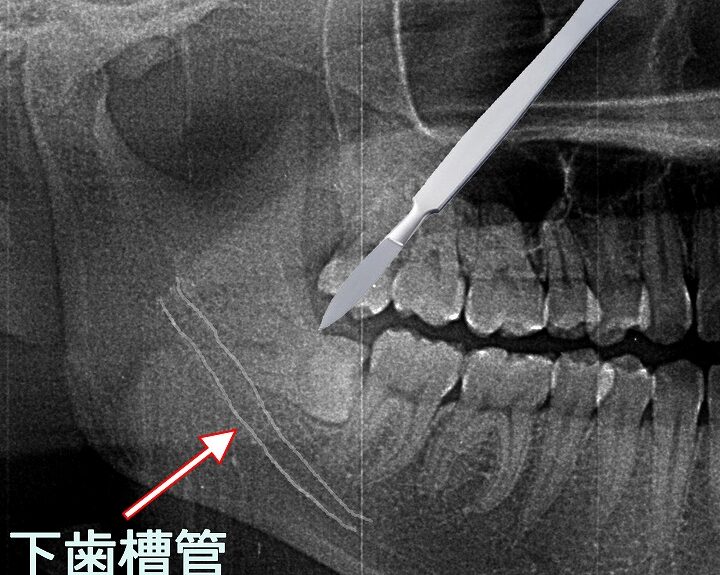

抜歯前には、レントゲン撮影を通じて親知らずの位置や周囲の構造を確認します。この情報は、手術方法や必要な麻酔の種類を決定するために重要です。

埋まっている親知らずがどのように生えているか、また周囲の組織への影響について正確な診断を受けることは非常に重要です。レントゲン撮影によって、その位置や状態を確認することで、治療方針が決定されます。このプロセスによって、不要なリスクを避けることができ、安全に抜歯を行うことが可能になります。